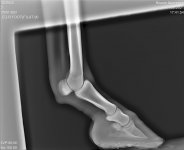

На рентгеновских снимках выявлено:

1) остеохондроз и чип в области путового сустава правой грудной конечности.

2) Старый перелом и изменение конфигурации края челночной кости с переостальной реакцией этого края.